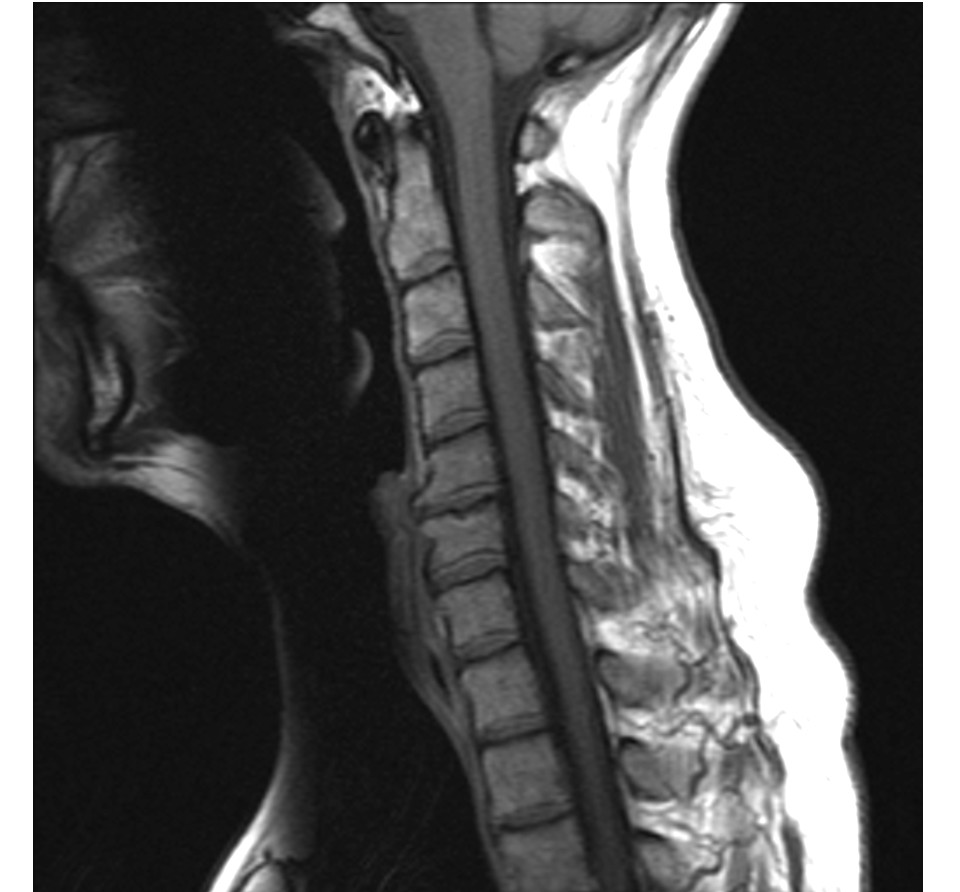

Cervical spine phantom with vertebral bodies C1-C7, intervertebral discs, spinal cord, nerve roots, and vertebral arteries